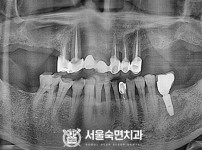

임플란트-전후사진3

치과를-선택할-때-꼭-확인하세요-서울숙면치과-임플란트-전후사진